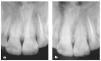

La exploración radiográfica confirmó las zonas de infiltración de caries y asimismo reveló un tratamiento endodóntico incorrecto en el diente número 22, en el que el acceso se había realizado exclusivamente a través de la cavidad de clase III mesial, con la consecuente lesión periapical asintomática (figura 33).

Figura 33 Radiografía del tratamiento endodóntico del diente número 22 con acceso a través de la cavidad de clase III mesial, con lesiones periapicales.

Figura 51 Control radiográfico de las restauraciones y la endodoncia (a) y control radiográfico de las restauraciones dos años después del tratamiento (b) con resolución de la imagen periapical translúcida.